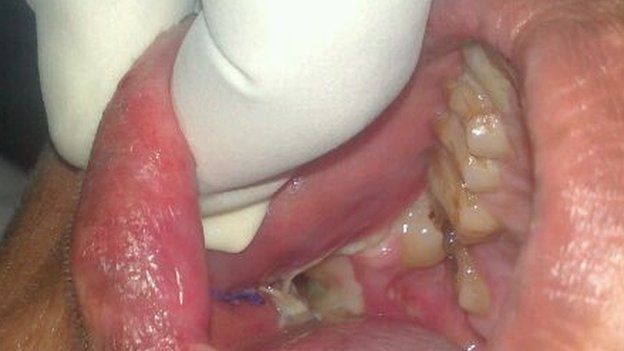

그의 턱에서 무려 232개에 달하는 치아가 자라고 있었기 때문이다.

진단 결과 애식은 복합 치아종을 앓고 있었는데 이 질병은 여러 치아가 자라는 종양이라고 한다.

원래 이 질병은 심하면 37개까지 나는 것이지만 그의 상태는 무려 7배나 되는 심각한 상황이었던 거이다.

애쉭은 장장 7시간에 걸친 대수술 끝에 치아 232개를 제거할 수 있었다. 그를 치료한 의사 반다나는 인터뷰를 통해 “30년 의사 경력에서 한 번도 이런 환자를 만나본 적이 없다”고 밝혔다.